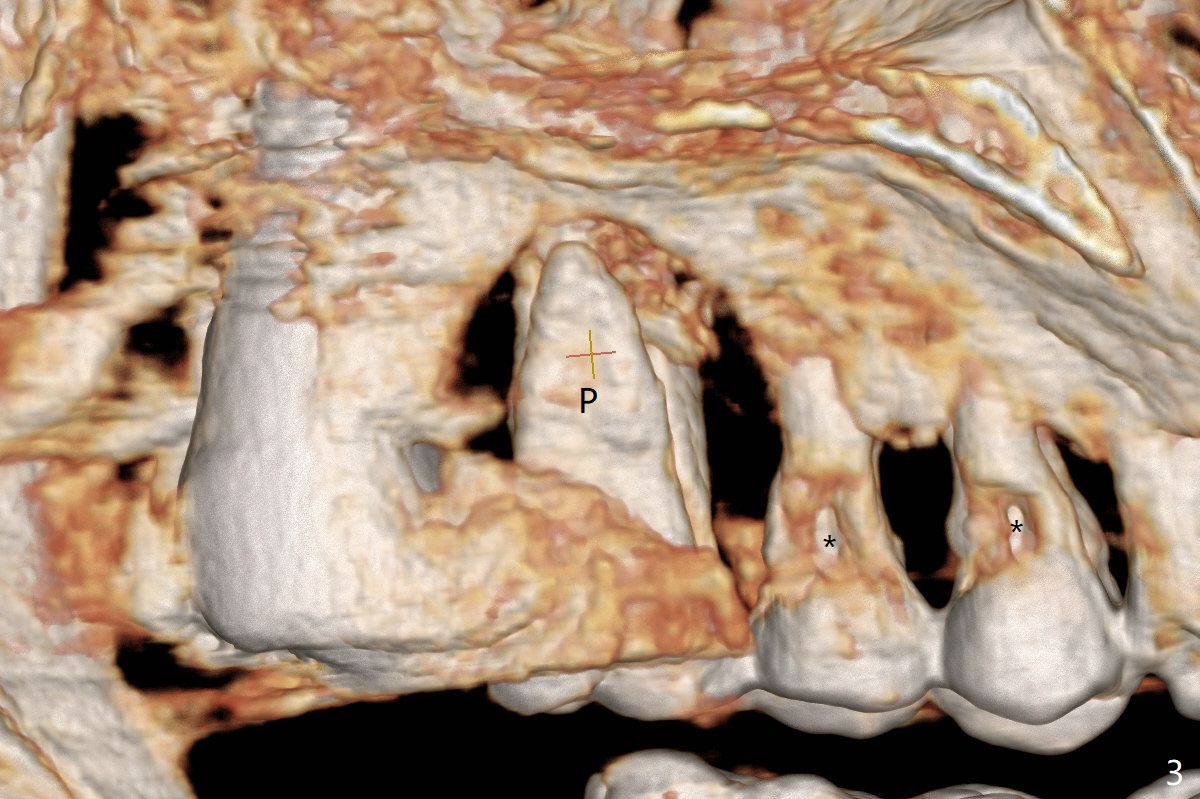

A 61-year-old woman requests implant at #14 because of mobility after exfolia-tion of the tooth #18 (Fig.1). Because of severe bone loss, especially palatal (Fig.2,3 P), osteotomy will be initiated with guide as buccal as possible (Fig.4). To reduce abutment screw loosening, a 5x11 mm tissue-level implant will be placed (Fig.5 blue (pink: abut-ment)).